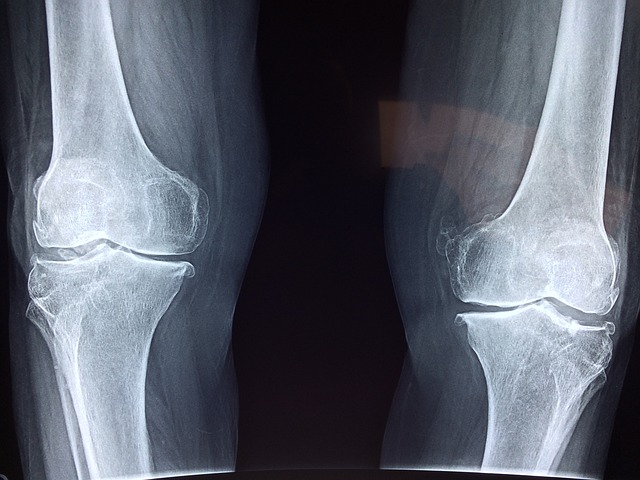

한쪽 무릎을 기준으로 대게 250~500만원선으로 책정이 되어있습니다.

병원마다 조금씩의 차이는 있을수 있으므로 정확한 진료를 받으시기 바랍니다.

무릎 인공관절 수술은 퇴행성 관절염이나 심각한 관절 손상을 겪는 환자들에게 효과적인 치료법입니다.